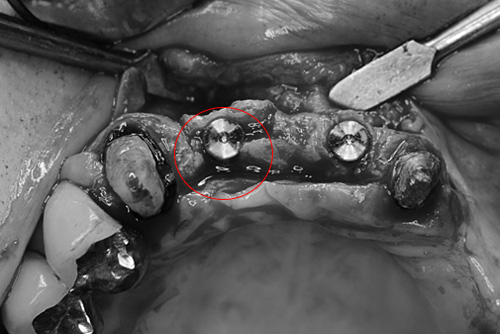

赤丸の部位にインプラントを埋入する予定です。

ピエゾサージェリー(超音波医療機器)で骨を安全に切削し、骨の頂上部にクサビのような形の特殊な器具を挿入し、慎重に二分割して骨を広げます。このときが一番神経が集中します。

骨を2分割しそのなかに、理想的な位置インプラントの埋入終わったところです